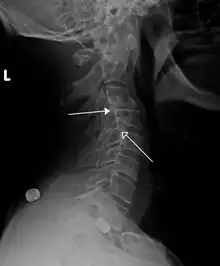

Grade 1 retrolistheses of C3 on C4 and C4 on C5

A retrolisthesis is a posterior displacement of one vertebral body with respect to the subjacent vertebra to a degree less than a luxation (dislocation). Retrolistheses are most easily diagnosed on lateral x-ray views of the spine. Views where care has been taken to expose for a true lateral view without any rotation offer the best diagnostic quality.